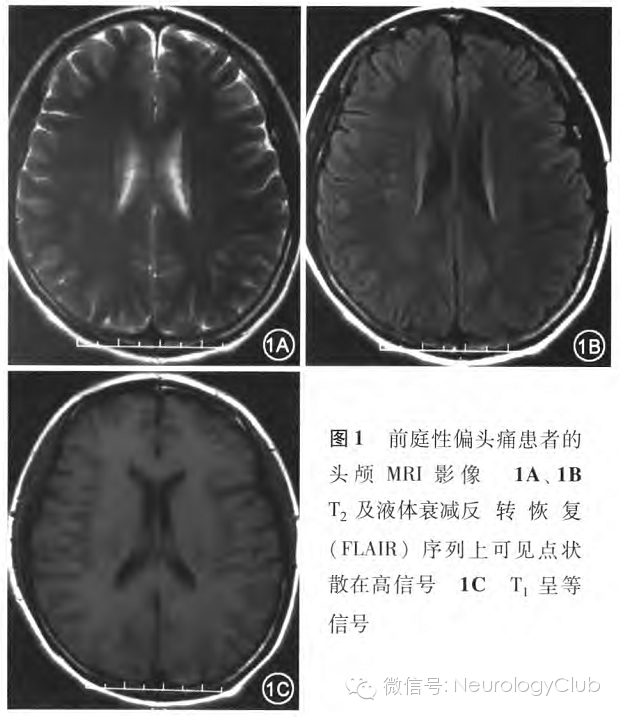

5.影像学表现:226例患者中162例(71.7%)行头颅CT检查,其中48例(29.6%)有腔隙性脑梗死(41例为60岁以上患者),11例(6.8%)有枕大池囊肿,2例(1.2%)发现动静脉畸形,余均大致正常。97例(42.9%)行头颅MRI检查,其中42例(43.3%)表现为T:以及液体衰减反转恢复(FLAIR)序列上在半卵圆中心可见点状散在高信号,而在T1呈等信号(图1)。

VM的病因及发病机制目前尚存在争议,主要有以下3个学说。其中皮层扩散性抑制(CSD)学说被大部分学者认可,认为皮层扩散性抑制一种自发传播的脑电波,可引起皮质去极化,导致神经细胞代谢减低、皮层血流减少,可导致眩晕和偏头痛。该机制已得到功能影像学研究的支持。还有部分学者认为一些神经肽(如降钙素基因相关肽、血清素、去甲肾上腺素和多巴胺)的释放可能通过不对称地活化或钝化神经元活性,引起功能性前庭平衡障碍,从而引发眩晕的发生。此外,也有学者认为内听动脉血管痉挛可解释眩晕同时伴发的耳蜗症状。笔者认为多种因素造成的微小动脉的痉挛缺血是患者头痛、眩晕症状的主要病因。本组病例中,头颅MRI检查显示有42例(43.3%)患者T2及FLAIR序列上在半卵圆中心出现散在高信号,而在T1上呈等信号,这与通常意义的腔隙性脑梗死表现是不同的,也验证了微小动脉的痉挛缺血的存在,但尚不清楚其中的因果关系。